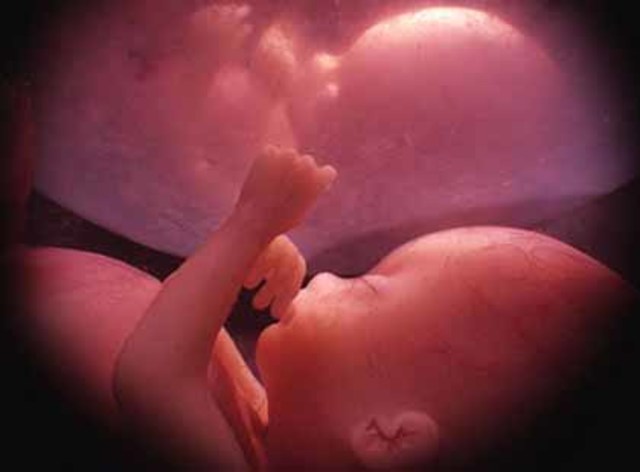

El feto se va a colocar para salir: con la cabeza hacia abajo.

El bebé ocupa ahora casi todo el sitio del útero y se entrena a abrir los ojos y a respirar. Sus movimientos, cada vez menos frecuentes.

Los huesos ya están desarrollados, pero aún son blandos y flexibles. Para dotarles de firmeza, el bebé comienza a almacenar hierro, calcio y fósforo.

En el sistema digestivo, el hígado, el estómago y el intestino van asumiendo progresivamente sus funciones.